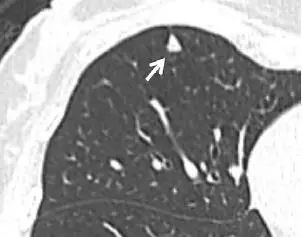

4、良性线状疤痕或淋巴组织

图片

图 4(a)层厚 1 mm 的 CT 横断面图像,显示邻近肺小裂的结节状阴影(箭头)。(b)冠状位重建 CT 图像,显示阴影为良性线状瘢痕或淋巴组织(箭头)。